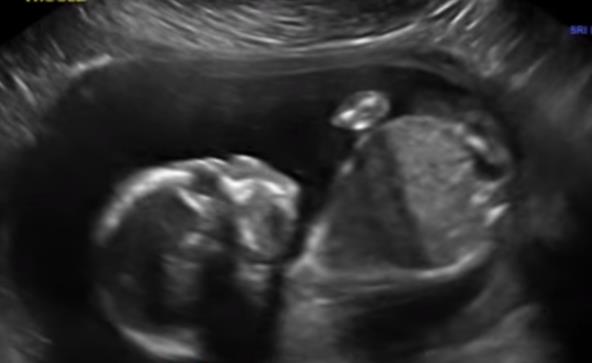

Tokom posmatranja bebe na ultrazvuku mogu se videti razne zanimljive situacije, ali ono što je jadan ultrazvuk snimio iznenadilo je i doktora koji je ovako nešto video prvi put iako ima karijeru dugu 20 godina.

Beba je sama sebe snažno udarala u lice, i bio je to vrlo čudan trenutak. Trudnica je rekla da je u početku bila zabrinuta da li beba može da se povredi, ali ju je doktor smirio rekaviši da je sve u redu.

Snimak ovog čudnog trenutka sa ultrazvuka podelili su na Jutjubu, pa pogledajte šta to beba radi: